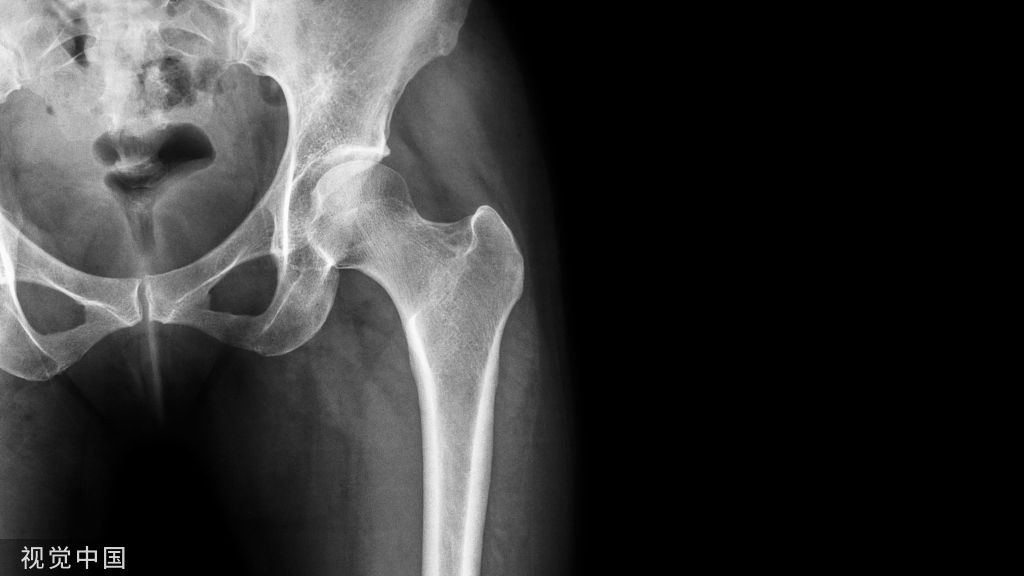

①局部血液供应:如果骨折部血液供应好,则骨折愈合快,如肱骨的外科颈(上端)骨折;反之,局部血液供应差者,骨折愈合慢,如股骨颈骨折。骨折类型也和血液供应有关:如螺旋形或斜形骨折,由于骨折部分与周围组织接触面大,因而有较大的毛细血管分布区域供应血液,愈合较横形骨折快。

老年、各种营养不良和内分泌等因素可引起全身性骨质疏松,表现为骨皮质萎缩变薄,骨小梁变细、数量减少。主要影响脊椎骨、股骨颈、掌骨等。老年尤其是绝经后老年妇女胸、腰椎压缩性骨折,股骨颈、肱骨上端及桡骨下端骨折较为多见。肢体瘫痪、长期固定或久病卧床等可引起局部废用性骨质疏松而造成骨折。